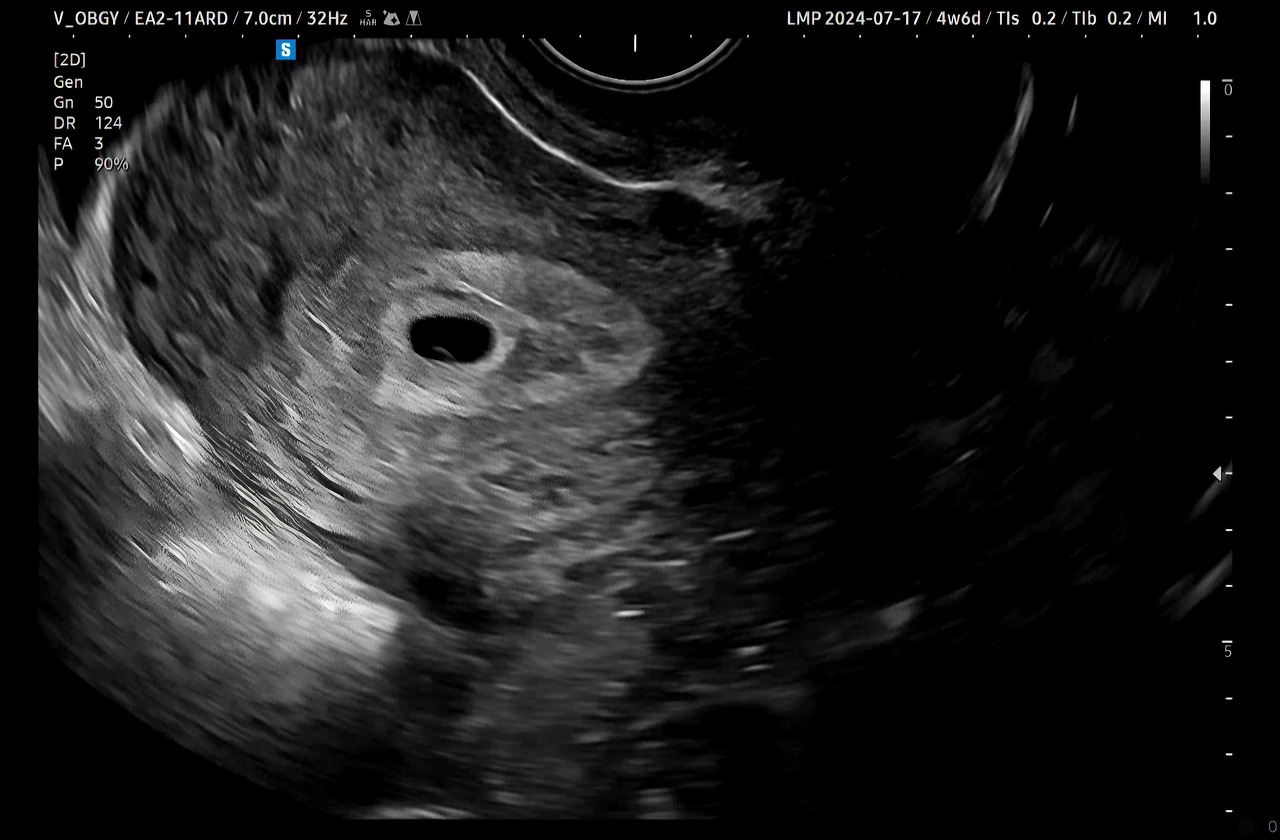

임신 사실을 확인한 다음날 얼떨떨한 채로 병원에 방문했더니 임신 4주 차였다. 아기집과 난황이 생겼음을 확인했다. 인스타그램에서 사진으로 종종 본 콩알만 한 아기집이 내 뱃속에도 있었다.